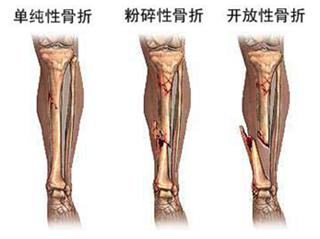

骨折在我们的日常生活中,时有发现,可以说是非常常见的一种疾病,对于骨折的治疗,基本上可以使患者…「 阅读全文 」